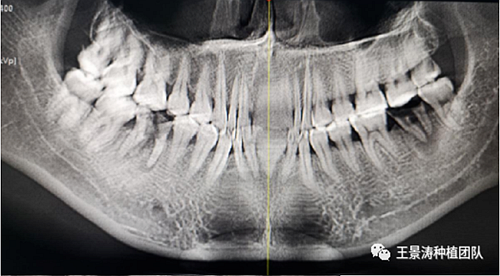

患者左側(cè)16慢性根尖周炎,17缺失。16根尖炎癥距上頜竇底較近,需內(nèi)提升,但是因?yàn)閮?nèi)提升后骨質(zhì)較薄所致植入深度過深,埋入式植入。17非埋入式種植。后期效果均可。